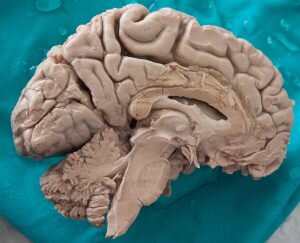

A partir de la década de los 60 del siglo pasado se dieron pasos agigantados en el estudio del cerebro, debido en gran medida a los avances tecnológicos. Por ejemplo, se desarrollaron escáneres que permitieron saber cómo es y cómo funciona este órgano. En años posteriores las investigaciones sobre él fueron enfocadas a la cognición humana (aprendizaje, memoria, percepción, etc.).